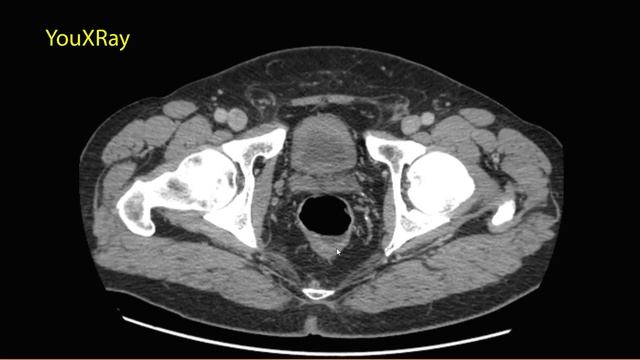

Рак кишечника на мрт 115 фото